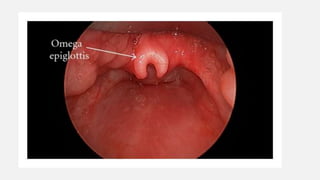

LARYNGOMALACIA

Most common congenital anomaly

Chief cause of chronic stridor in infancy

Clinical features: inspiratory stridor; increase in supine or crying

position

Flexible endoscopy:

● Omega shaped epiglottis

● Short aryepiglottic folds

● Partial collapse of a flaccid supraglottic airway with

inspiration